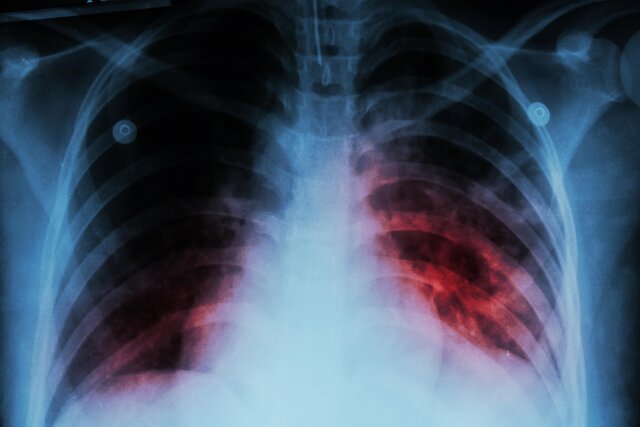

وی افزود: بیماری سل که از قدیمی‌ترین بیماری‌های شناخته شده برای بشر است، همچنان به عنوان یکی از مرگبارترین بیماری‌های عفونی در جهان شناخته می‌شود.

عضو هیات علمی دانشگاه علوم پزشکی جندی شاپور اهواز گفت: با وجود پیشرفت‌های پزشکی و درمانی و با اینکه سل قابل درمان است اما متاسفانه این بیماری ، همچنان جان میلیون‌ها نفر را در سراسر جهان می‌گیرد.

وی ادامه داد: بر اساس آمارها، هر ۱۰ ثانیه یک نفر به این بیماری مبتلا می‌شود و هر ۲۰ ثانیه یک نفر جان خود را از دست می‌دهد. این بدان معنا است که سالانه حدود ۱.۵ میلیون نفر در اثر سل، جان خود را از دست می‌دهند.